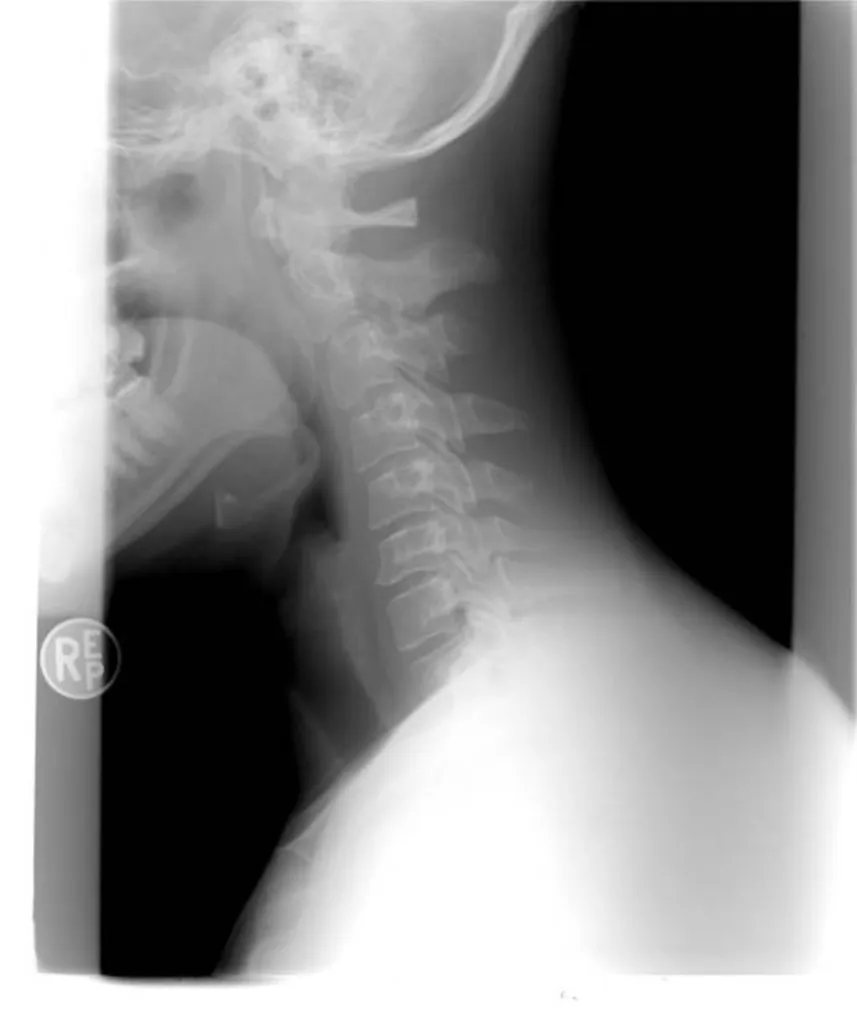

Indemnisation entorse cervicale suite à accident de la route Toulon et Var 83

Avocat pour l'indemnisation de dommage corporel du conducteur victime d'accident de la route ayant subi un "coup du lapin" ou entorse cervicale lors d'un choc arrière à Marseille

Le conducteur victime d'un accident de la route ayant subi un  "coup du lapin" ou entorse cervicale lors d'un choc arrière à Marseille a droit à l'indemnisation de son dommage corporel sur le fondement de la loi du 5 juillet 1985. L'assistance par un avocat est toutefois nécessaire pour être bi...